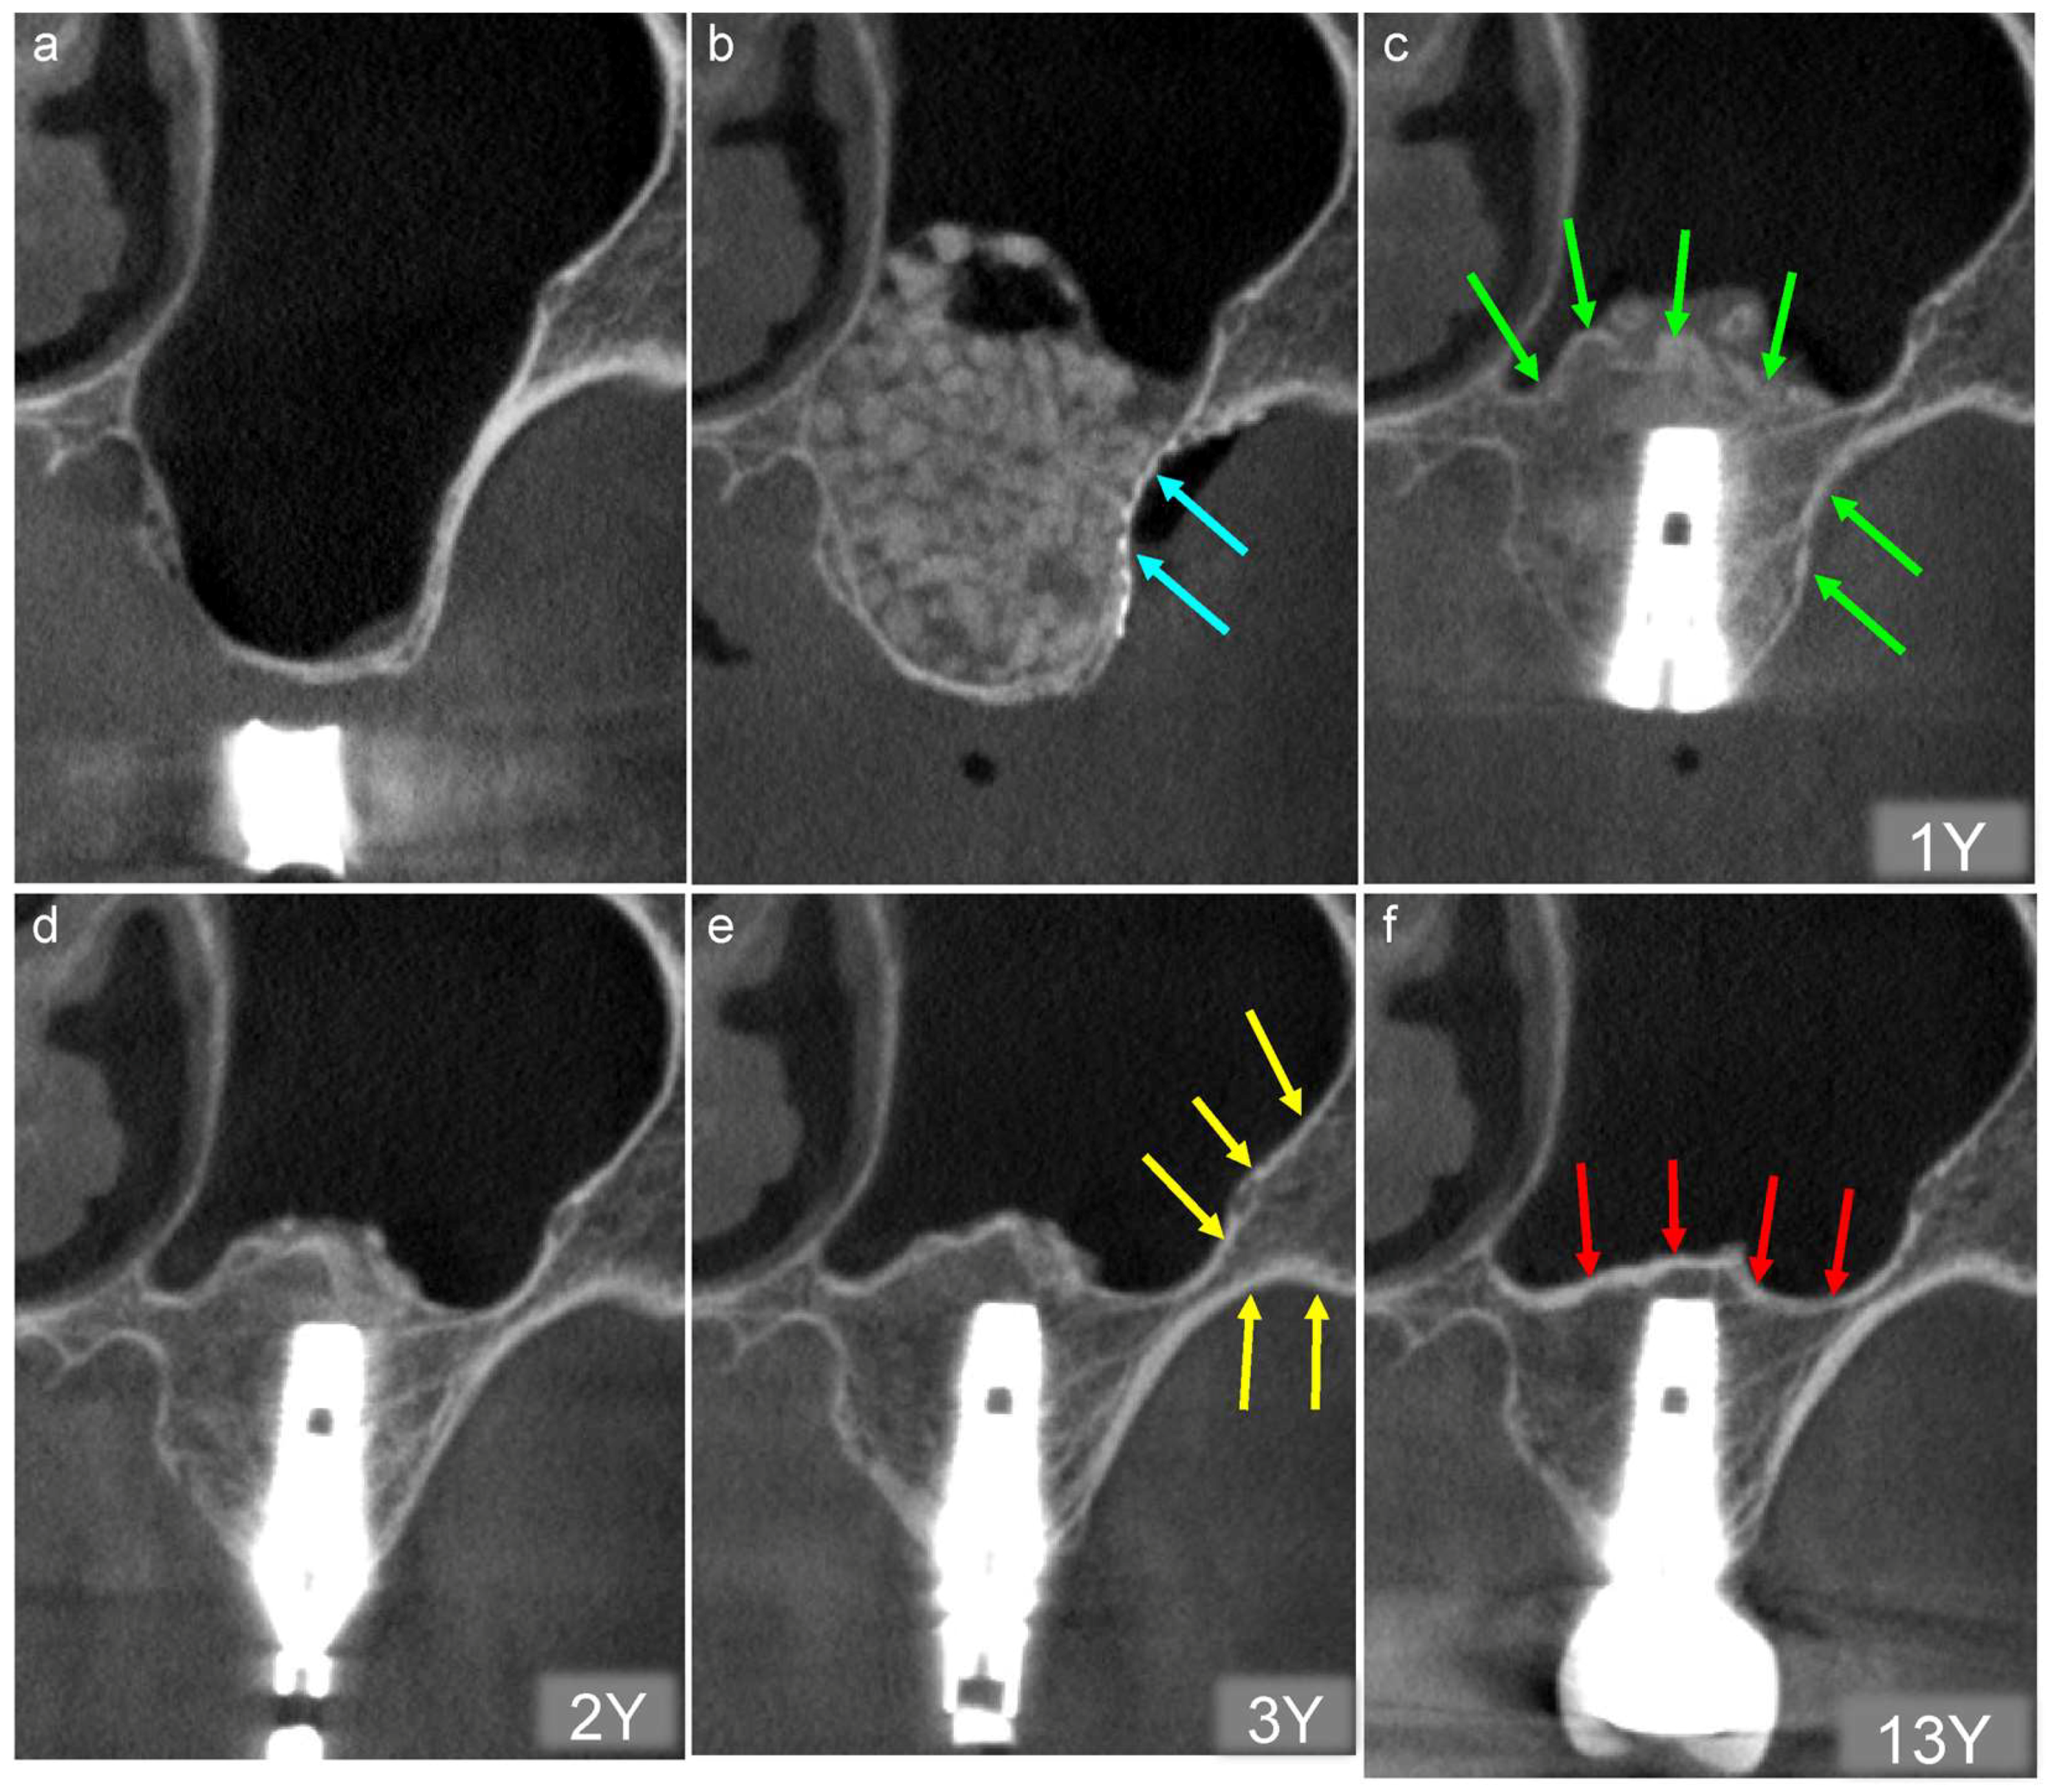

Figure 8.

(a) Buccolingual section of the CT image obtained before sinus floor elevation. Bone height is <1 mm. (b) CT image acquired on the day of the surgery. The β augmented area is filled with TCP granules, and the bony window is covered tightly with a titanium mesh plate and microscrews (blue arrows). (c) Tapered-type implants were placed one year postoperatively, and initial fixation was achieved. A clear white line and radiopaque line resembling the cortical bone can be observed at the newly formed bottom of the maxillary sinus and bony window, respectively (green arrows). 1Y; one year follow-up (d) The radiopacity of the augmented area is divided into two types two years postoperatively: cortical and cancerous. 2Y; two years follow-up (e) The radiopacity of the augmented area shows a density similar to that of the original bone (yellow arrows) three years postoperatively. 3Y; three years follow-up (f) The bottom line of the maxillary sinus decreased slightly because of pneumatization 13 years postoperatively (red arrows). 13Y; thirteen years follow-up.

- Tapered-type implants were placed to achieve initial fixation one year after sinus floor elevation. Small particles of β-TCP granules can be observed around the implant. However, a clear white line and radiopaque line similar to the cortical bone can be observed at the newly formed bottom of the maxillary sinus and bony window, respectively (Figure 8c, green arrows).

- The radiopacity of the augmented area can be divided into two types two years after sinus floor elevation: cortical and cancerous bone. Tiny particles of β-TCP granules can be observed around the implant (Figure 8d).

- The β-TCP granules have disappeared three years after sinus floor elevation, and the augmented area shows cortical and cancerous bone-like radiopacity. The radiopacity of the augmented area is similar to that of the original bone (Figure 8e, yellow arrows). This suggests that new bone tissue has likely formed in the augmented area, mirroring the density of the original bone.

- The radiopacity of the augmented area remained almost unchanged compared with that at three years postoperatively 13 years after sinus floor elevation. Thus, an active bone transformation of the β-TCP granules continues for three years after sinus floor elevation. This results in the regeneration of the critical and cancerous bone. However, the line at the bottom of the maxillary sinus descended slightly due to pneumatization (Figure 8f, red arrows), suggesting that the newly formed bone is natural bone.